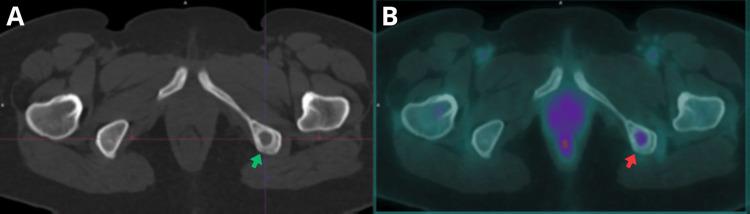

Medullary thyroid carcinoma (MTC) is a rare neuroendocrine tumor with variable clinical presentation, posing both diagnostic and therapeutic challenges. Disease recurrence is common and may manifest solely as elevated tumor markers in the absence of clinical findings or positive morphological imaging. We present the case of a 56-year-old woman diagnosed with MTC in 2011, treated with total thyroidectomy and adjuvant therapy. In 2021, a locoregional recurrence was detected, requiring left-sided neck dissection. During follow-up in 2025, elevated tumor markers were identified despite negative findings on computed tomography (CT). Consequently, an F-fluorodeoxyglucose (FDG) positron emission tomography (PET)/CT was performed, revealing disease recurrence with multiple lesions suggestive of bone metastases. This case underscores the value of F-FDG PET/CT in the follow-up and detection of MTC recurrence.

摘要

甲状腺髓样癌(MTC)是一种罕见的神经内分泌肿瘤,临床表现多样,给诊断和治疗带来挑战。疾病复发很常见,可能仅表现为肿瘤标志物升高,而无临床症状或形态学影像学阳性表现。我们报告一例56岁女性病例,该患者于2011年被诊断为MTC,接受了甲状腺全切除术及辅助治疗。2021年,检测到局部区域复发,需要进行左侧颈部清扫术。在2025年的随访中,尽管计算机断层扫描(CT)结果为阴性,但肿瘤标志物升高。因此,进行了氟脱氧葡萄糖(FDG)正电子发射断层扫描(PET)/CT检查,结果显示疾病复发,有多个提示骨转移的病灶。该病例强调了F-FDG PET/CT在MTC复发随访和检测中的价值。